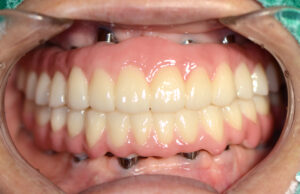

모든 치아를 발치한 후

임플란트를 진행하였으며

상악 6개, 하악 6개를 식립하였어요.

하악의 경우 픽스쳐를 식립하기에

잇몸뼈가 부족하여 치조골이식을

추가로 진행하여 안정적으로 진행했어요.

치료후 사진을 보시게 되면

구강에 적합한 모양과 형태로

완성된 모습을 보실 수 있어요.

상하악이 동시에 진행되는

풀아치임플란트는 보철물의 각도나 위치,

교합 관계를 정확하게 맞추는 것이 중요한데

제대로 맞지 않게 제작이 되면

저작이 불편하고 안면 비대칭을

유발할 수 있기 때문에

보철물제작은 그만큼 중요한 과정이에요.

환자분께서는 진작 임플란트를

할걸 그랬다고 좋아하셨으며

심미적, 기능적인 부분에서

모두 흡족해하셨어요.😁